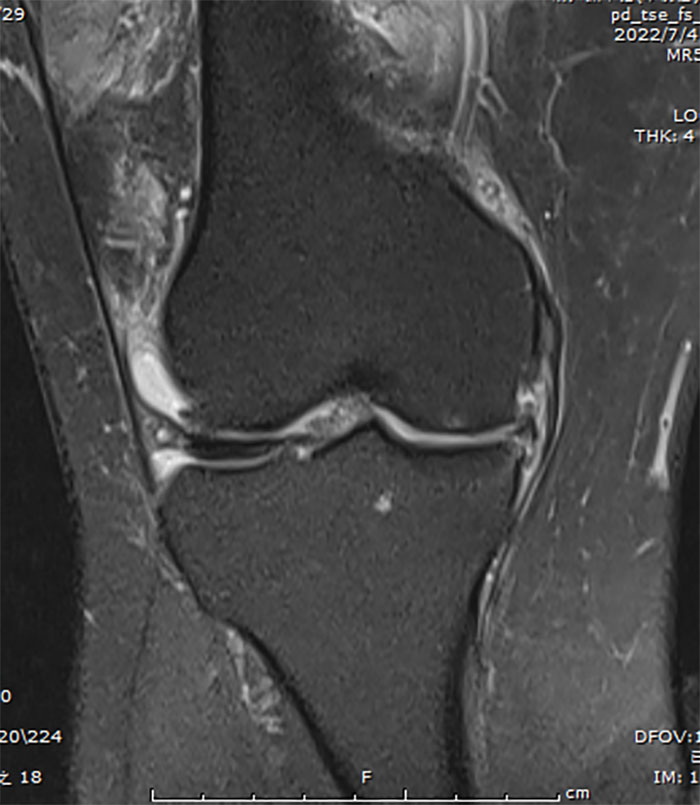

關節(jié)外一科(骨四科)主任白玉明接診后,仔細詢問病史,并進行查體及對影像學資料的審閱,診斷為右膝(內側)單間室骨性關節(jié)病、內側半月板撕裂伴外突。MRI顯示:右膝內側間室軟骨明顯磨損變薄,基本是骨磨骨狀態(tài),并伴隨軟骨下骨骨髓水腫。

以往傳統(tǒng)治療膝骨性關節(jié)病的方式是全膝關節(jié)置換(TKA),對比于單髁關節(jié)置換,全膝關節(jié)置換創(chuàng)傷大、恢復慢、本體感覺差,考慮患者右膝髕股關節(jié)及外側間室無明顯疼痛癥狀,且MRI顯示:外側半月板、軟骨及前交叉韌帶基本完好,膝關節(jié)屈伸功能無受限,關節(jié)外一科(骨四科)手術團隊為患者選擇了膝關節(jié)單髁置換(UKA),在征得患者及家屬同意后,制定了詳細周密的手術方案。